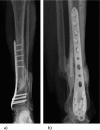

Chronic osteomyelitis represents a progressive inflammatory process caused by pathogens, resulting in bone destruction and sequestrum formation.It may present with periods of quiescence of variable duration, whereas its occurrence, type, severity and prognosis is multifactorial.The 'gold standard' for the diagnosis of chronic osteomyelitis is the presence of positive bone cultures and histopathologic examination of the bone.Its management remains challenging to the treating physician, with a multidisciplinary approach involving radiologists, microbiologists with expertise in infectious diseases, orthopaedic surgeons and plastic surgeons.Treatment should be tailored to each patient according the severity and duration of symptoms, as well as to the clinical and radiological response to treatment.A combined antimicrobial and surgical treatment should be considered in all cases, including appropriate dead space management and subsequent reconstruction. Relapse can occur, even following an apparently successful treatment, which has a major impact on the quality of life of patients and is a substantial financial burden to any healthcare system. Cite this article EFORT Open Rev 2016;1:128-135. DOI: 10.1302/2058-5241.1.000017.